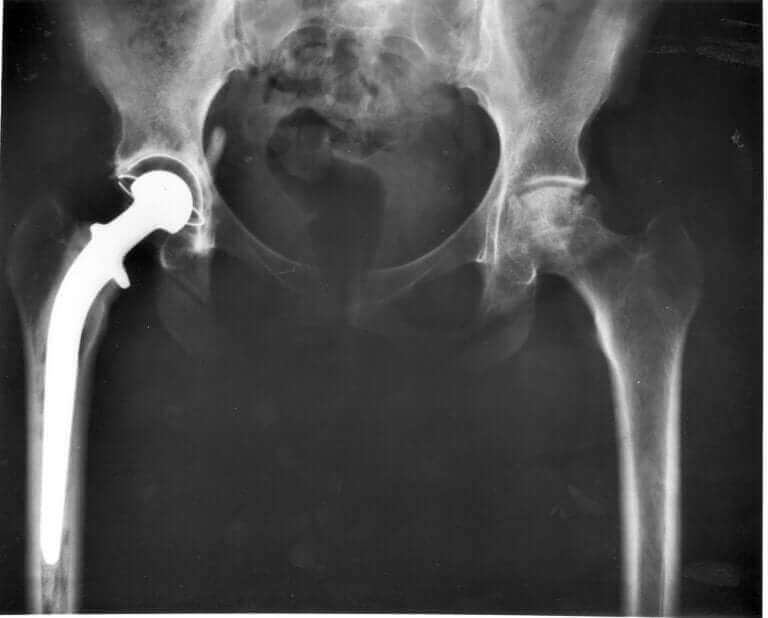

Din dyrlæge vil kigge på din kats hofteled og tage røntgenbilleder for at identificere det præcise problem. Hvis din kat faktisk har hofteledsdysplasi, er der nogle behandlinger derude, der kan lindre smerterne og mindske symptomerne. Desværre findes der ikke nogen kur imod det endnu.

Nogle af disse behandlinger involverer ting som fysisk terapi og forbud mod visse aktiviteter, antiinflammatorisk medicin (oralt eller indsprøjtninger,) og vægtkontrol. I mere alvorlige tilfælde kan det være nødvendigt med en operation af hoften, der kan udskiftes.